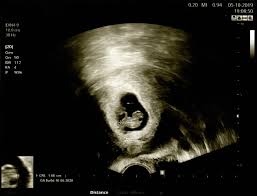

Cat Ia Bebe In Greutate In Ultima Luna De Sarcina